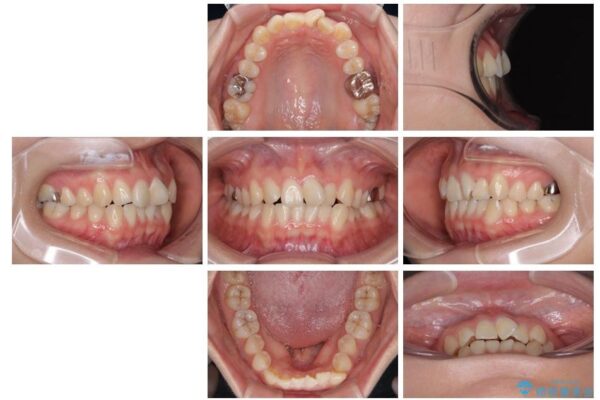

治療前

• 前歯のねじれ・ガタガタを10か月で改善!20代女性の矯正治療|クリアブラケットでむし歯になりにくい歯並びへ改善 治療前画像

診察の結果、上下の前歯部に**叢生(そうせい/歯のガタガタ・重なり)**が認められました。

特に上の前歯にはねじれや重なりがあり、審美的にも清掃性にも影響している状態でした。

また、上顎前歯の重なっていた部分にはむし歯が見つかり、治療中に適切な処置を行っています。